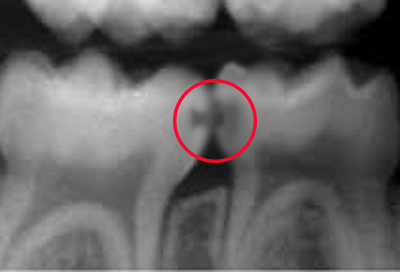

健康に見える乳歯

一見すると全く虫歯がないようにみえます。

実はレントゲンで見てみると、歯と歯の間に大きな虫歯が隠れています。

このような隠れ虫歯は、小児歯科に慣れていない歯医者ではよく見落とされてしまい、虫歯なしと診断されてしまいます。